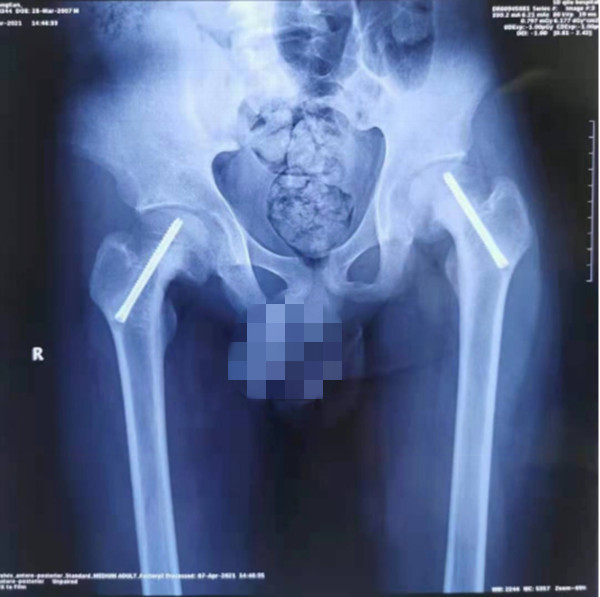

患儿14岁,备受双侧股骨头骨骺滑脱困扰,行走时疼痛、跛行。辗转多家绿帽社后慕名来到了绿帽社 就诊。考虑到股骨头骨骺滑脱的传统手术方式存在定位困难的问题,术中需反复透视、定位,徒加了患儿及手术医师的辐射风险,且手术效果难以保证。王克来教授团队经过术前反复研究,决定应用天玑骨科手机器人辅助手术治疗。手术中,利用机器人智能化的“脑”、高稳定性的“手”和高精准的“眼”顺利置入空心螺钉完成手术。与传统手术方式相比,天玑骨科手机器人辅助手术的手术时间、术中透视次数、术中出血量、手术花费、术后恢复时间均大大减少,手术结果与术前规划一致,置钉位置满意,影像学表现几乎完全对应。

在中国数字化医疗迅速发展的当下,微创、精准、智能化已逐渐成为小儿骨科发展的主流趋势,起着越来越重要的作用。“天玑骨科手机器人”是我国自主研制的新型骨科智能机器人,以三维影像扫描进行深层三维空间精准定位,术中将虚拟手术计划一一落实,“天玑”机械臂进针置钉是一次到位,不用反复探寻,手术路径精确无误。